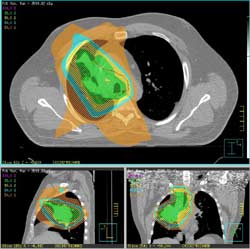

Then, a computer program studies the 3D image and designs radiation beams that match the shape of the tumor.

- During treatment, beams from many directions precisely match the tumor's height, width, and depth.

- The linear accelerator moves in a circular fashion around the tumor area.